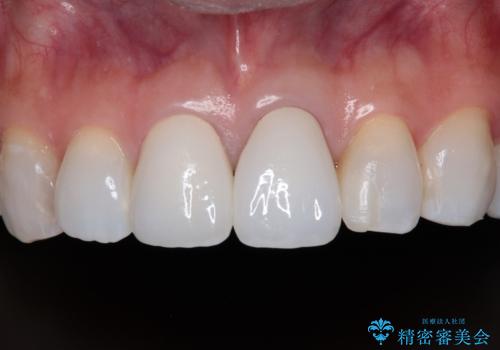

元々の歯の色が非常に白く、セラミッククラウンの色調を合わせるのに苦労しましたが、最終的に大変満足いただけるクラウンを装着することができました。